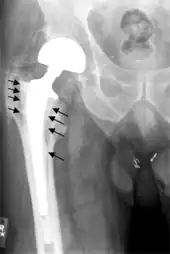

Hip prosthesis displaying aseptic loosening (arrows)

Hip prosthesis zones according to DeLee and Charnley,[42] and Gruen.[43] These are used to describe the location of for example areas of loosening.

On radiography, it is normal to see thin radiolucent areas of less than 2 mm around hip prosthesis components, or between a cement mantle and bone. These may indicate loosening of the prosthesis if they are new or changing, while areas greater than 2 mm may be harmless if they are stable.[44] The most important prognostic factors of cemented cups are absence of radiolucent lines in DeLee and Charnley zone I, as well as adequate cement mantle thickness.[45]